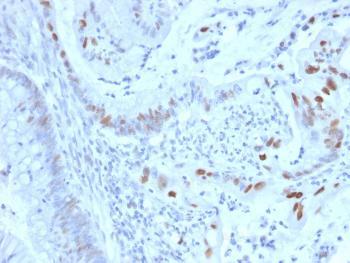

Fig. 1: Formalin-fixed, paraffin-embedded human Colon Carcinoma stained with Cyclin E Mouse Monoclonal Antibody (CCNE1/2460).

Flow Cytometry (1-2ug/million cells); Immunofluorescence (1-2ug/ml); Western Blot (1-2ug/ml); ,Immunohistochemistry (Formalin-fixed) (1-2ug/ml for 30 minutes at RT),(Staining of formalin-fixed tissues requires heating tissue sections in 10mM Tris with 1mM EDTA, pH 9.0, for 45 min at 95 °C followed by cooling at RT for 20 minutes),